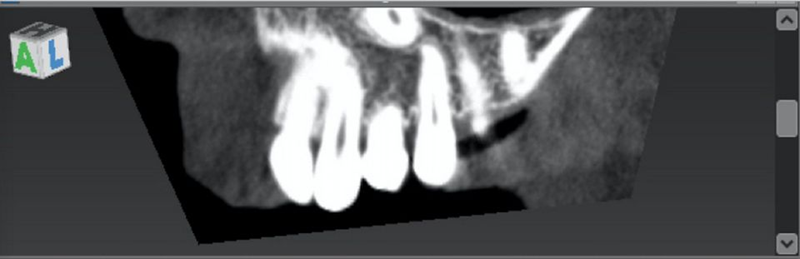

锥形束计算机断层扫描 (CBCT) 的放射线检查显示,乳牙根部极度缩小,左上恒尖牙阻生,乳牙部位有厚厚的皮质骨和足够的骨小梁,以及在那里放置植入物的可行性(图9-10)。

Fig. 9: Cone Beam Computed Tomography (CBCT) exam shows the presence of the impacted canine.

Fig. 10: CBCT showed a thick cortical bone and adequate trabecular bone in the deciduous tooth site, as well as the feasibility of placing there an implant.